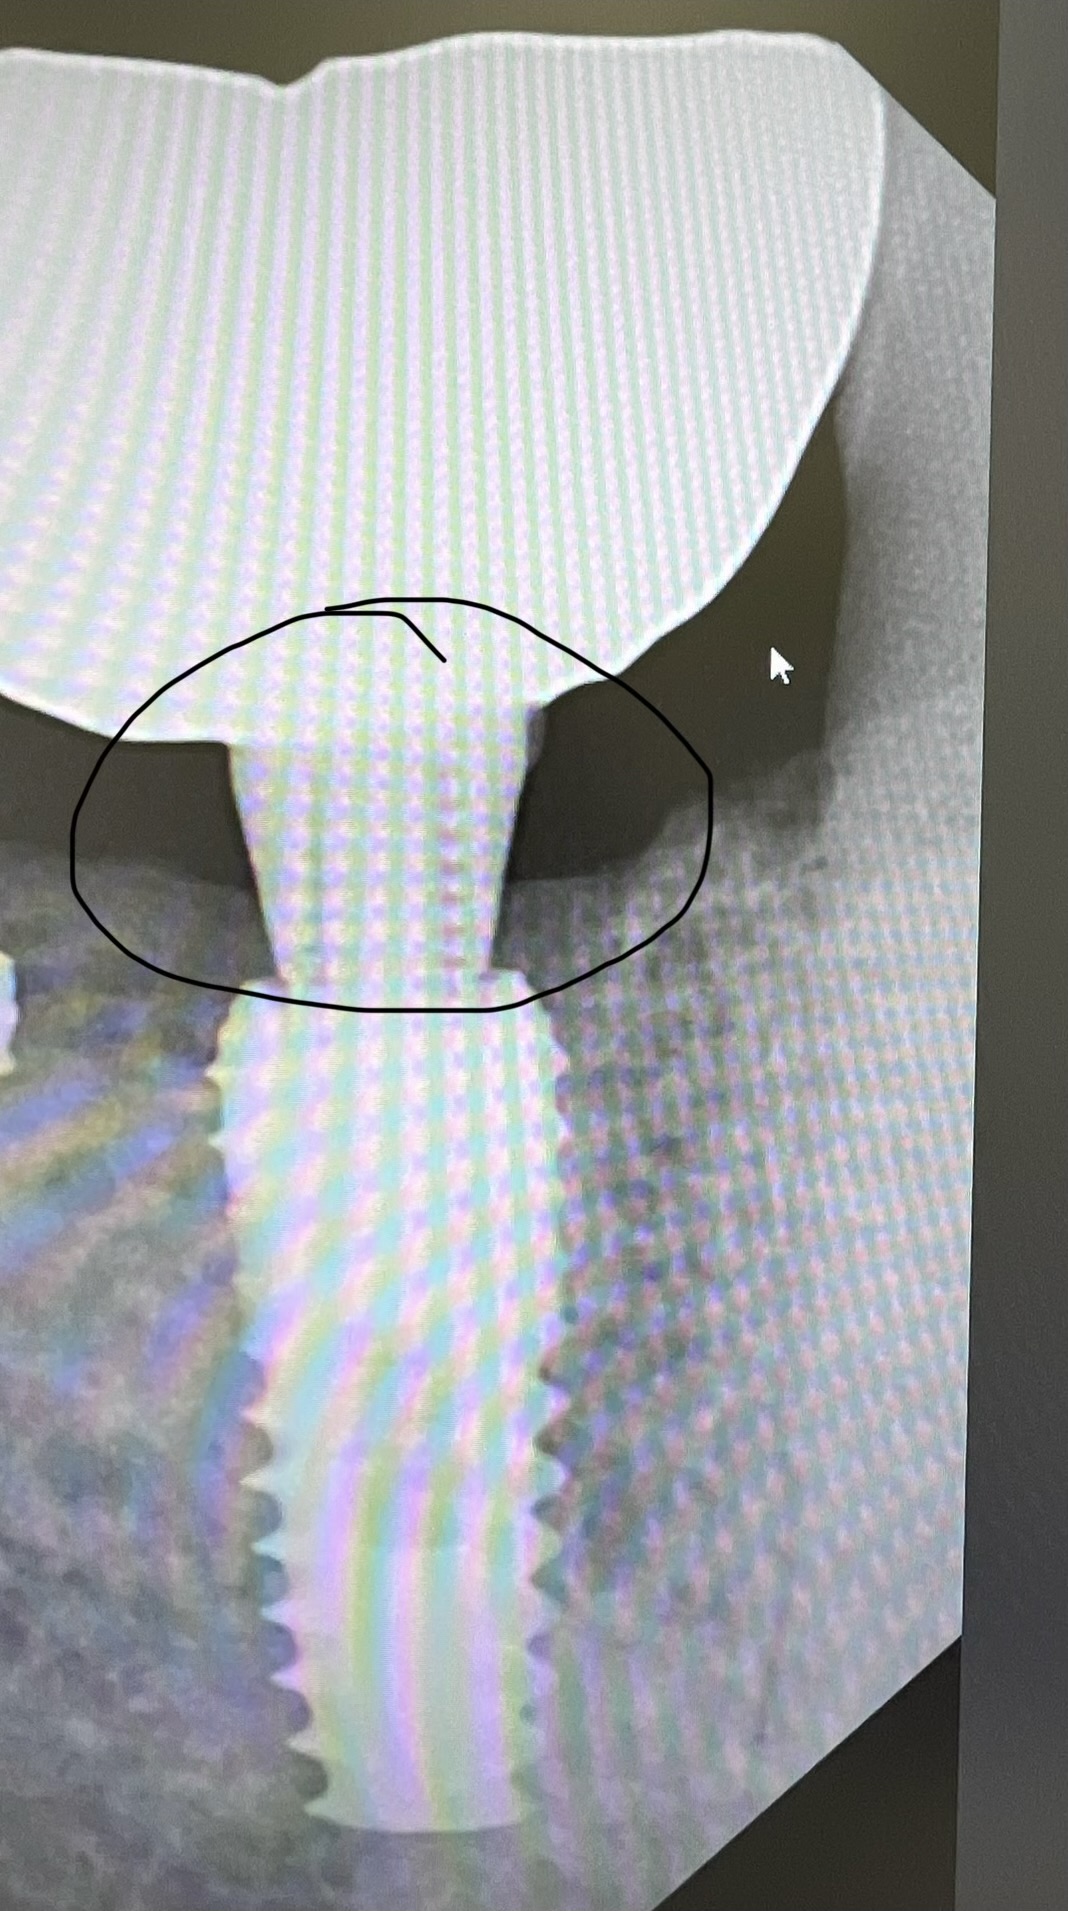

Implants placed too close: Is this restorable?

I am feeling really humble. I’ve placed multiple implants and thinking this should be a straightforward case. I was wrong. I know it’s poorly planned and freehand did not go well. Are these restorable? Should I explant and redo? If I do remove these, how easy is it to remove these?